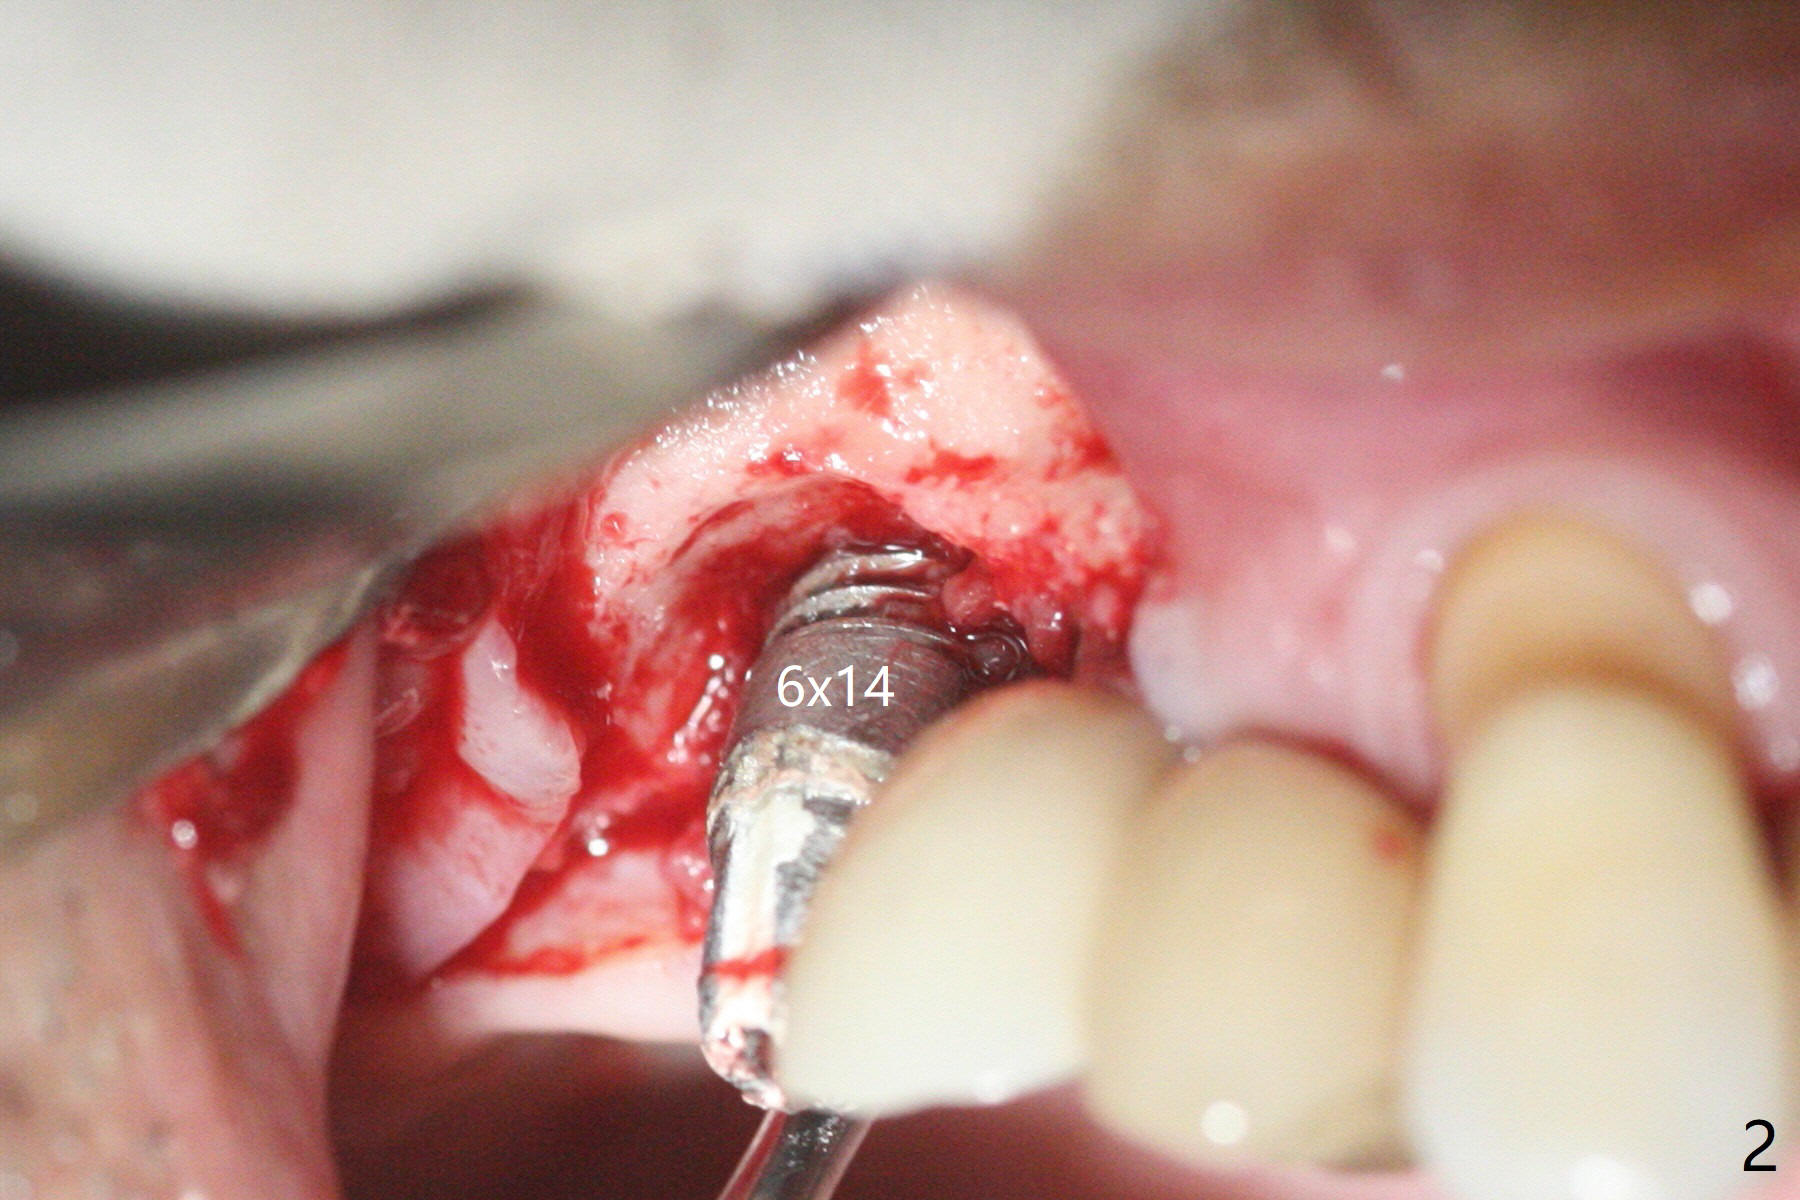

术前检查发现右上6颊侧牙龈沟有脓性分泌物(图一),翻瓣显示骨质吸收(图二),曾经植骨三次,只好去骨,取出植体,远中颊侧轻度上颌窦穿孔(图三:>),塞入小块PRF膜后,患处放置粘性骨粉,覆盖两块PRF膜和一片GEM Cap(9-12月吸收膜),三者近中一端有一个洞,挂在5基台上固定。术后即刻根尖片显示骨粉充填穿孔(图四:>),6缺失区以及5远中(*)。术后第二天牙周敷料脱落,术后16天病人回来,要求剪除缝线,伤口尚未关闭,下面黄色骨粉好像挺牢靠;为了减少继续骨粉丧失,使用树脂敷料(图五)。术后四周敷料稳定,牙龈健康,但是不放心下面伤口愈合,暂时没有撤去敷料。术后四个月骨质高度不足(图六至八),上颌窦膜薄,提升不容易,可放置5x7.3毫米植体(IBS),PRF。Return to No Caries 4 Placement 种植杂谈 Xin Wei, DDS, PhD, MS 1st edition 01/26/2021, last revision 07/30/2021